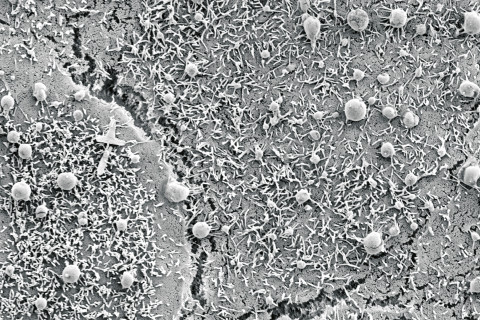

Cancer can spread and form metastases via vesicles. In addition to the vesicle content, molecules attached to their surface also play a role, such as the extracellular sugar compound hyaluronan. “Hyaluronan may steer the transportation of vesicles to certain target cells, but it can also help in drug targeting,” Academy Research Fellow Kirsi Rilla says.

Her research group discovered that hyaluronan-covered vesicles are formed especially when the production of hyaluronan is activated, which is often the case in many cancers and inflammations.